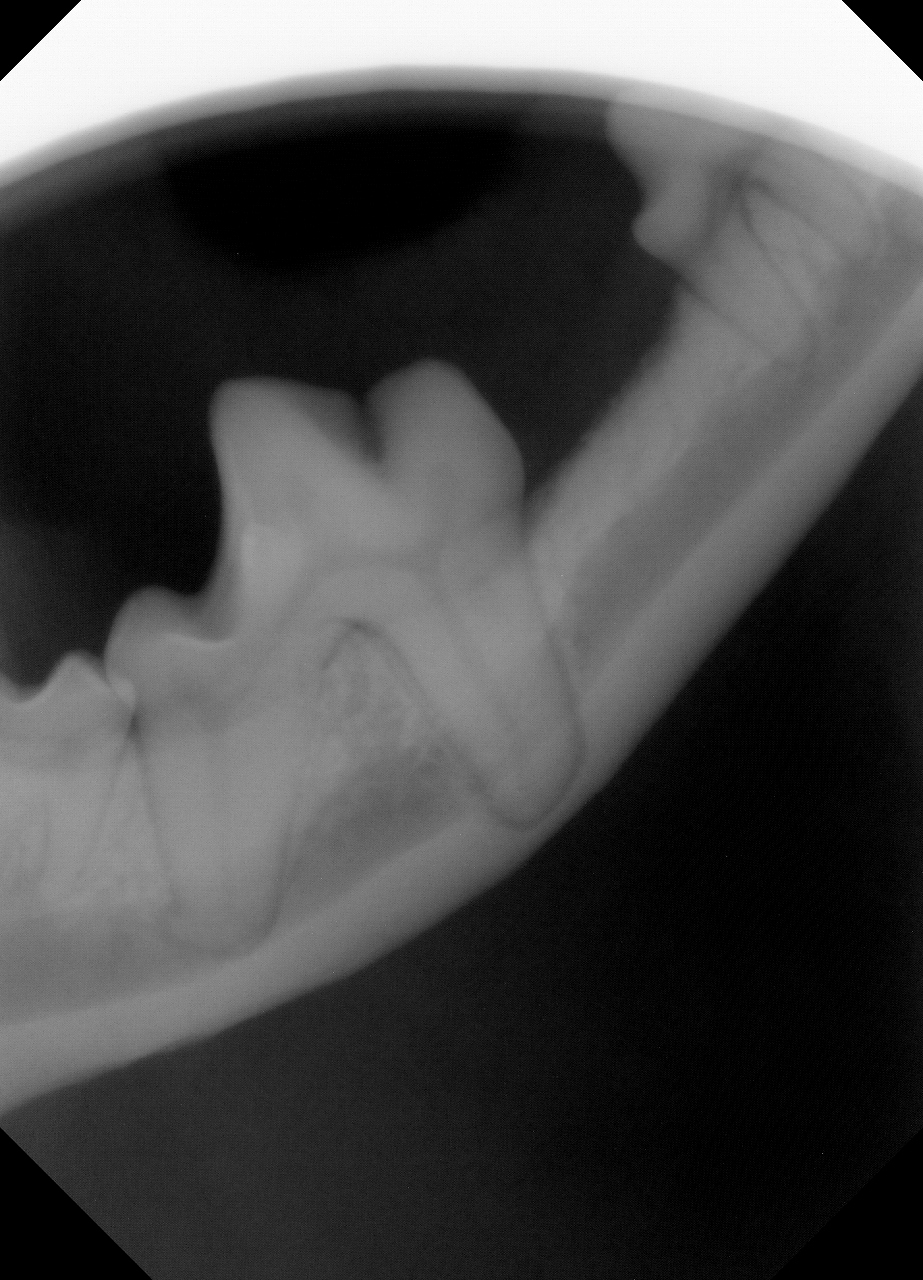

その次に歯科用レントゲンで歯とアゴの骨のレントゲンを撮影してみたところ......